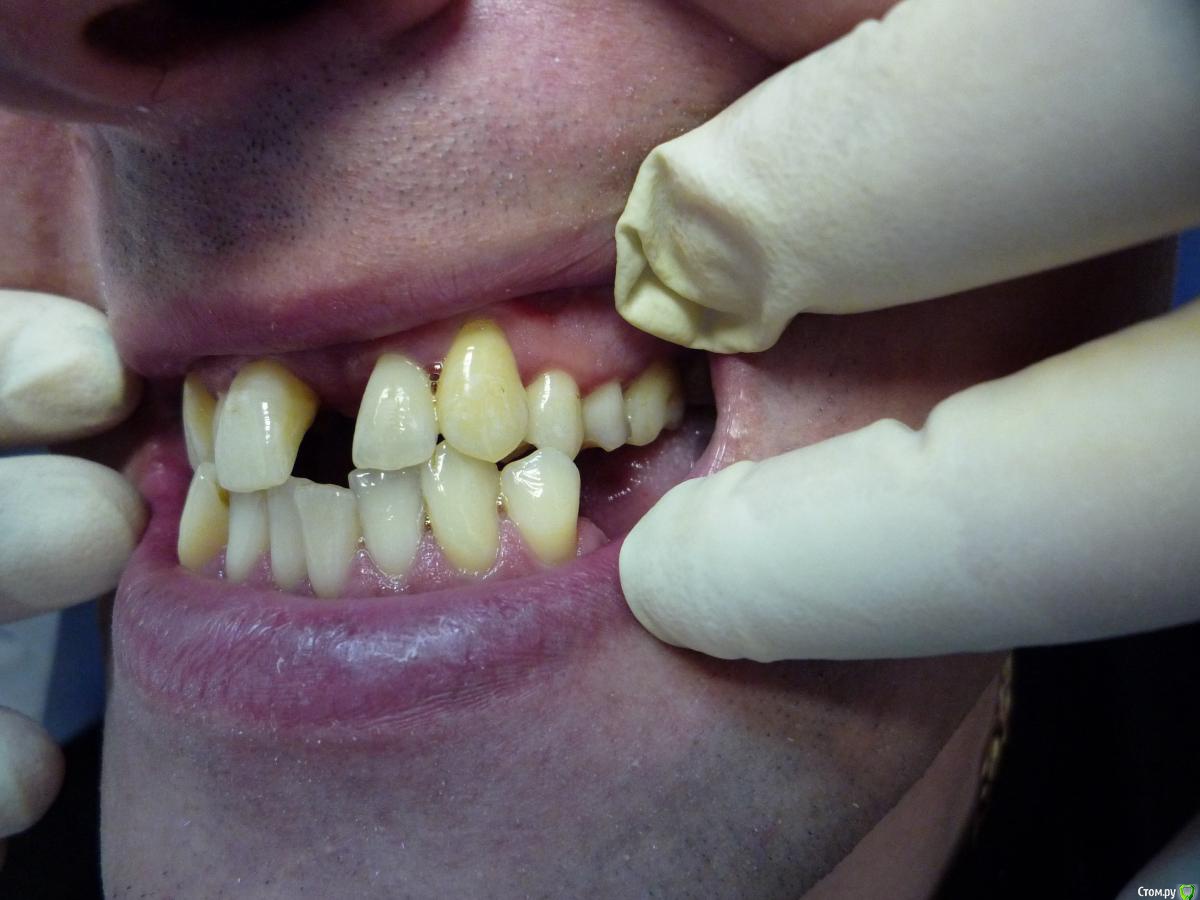

Jeniaspb Опубликовано 20 июля, 2015 Поделиться Опубликовано 20 июля, 2015 Пациент 32 года. Фото к сожалению только те, что есть. По ТРГ верхняя микрогн и нижняя прогнатия, протруз резцов в/ч 132^ и ретрузия резцов н/ч 68^, а так же переднее положение головки н/ч. Идеально сделать гнатич хирургию, но пациент идет в полный отказ, в связи с чем имеются следующие мысли:1) провести ТЭНС терапию с определением положения н/ч, в надежде на то, что она сместится хоть чуточку назад.2) если н/ч сместится каппа на н/ч с последующ окклюз накладками3) б/с на нижн зубн ряд и попыткой смещения дистально премоляров для освобожд места резцам4) б/с на в/ч и попытки камуфляжа этого всего...5) имплантация и затем протезирование.Вопрос самый главный:на сколько велики мои шансы сделать обратное перекрытие, которое я не смогу вернуть?) Ссылка на комментарий